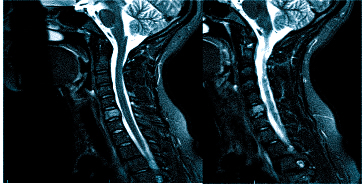

Если результаты МРТ недостаточны, могут быть назначены дополнительные исследования, такие как МРТ шейного отдела позвоночника, а также:

Важно! Если причина головной боли не ясна после МРТ, может потребоваться дополнительная диагностика шейного отдела позвоночника.

МРТ при головных болях (в трех проекциях) позволяет получить объемные изображения, что помогает выявить даже незначительные изменения и отличить патологию от нормы.

Причин головной боли множество, и не всегда их можно определить без современных методов визуализации. Цефалгию могут вызывать повышенное внутричерепное давление, сосудистые мальформации, опухоли и посттравматические осложнения. Выбор между МРТ и КТ зависит от предполагаемой патологии. Оба метода взаимодополняют друг друга, но решение о том, что лучше в конкретном случае, принимает врач, учитывая жалобы, показания и противопоказания. МРТ и КТ с контрастом обеспечивают сопоставимое качество снимков, но используют разные принципы построения изображений. Чем раньше будет установлена причина и начато адекватное лечение, тем выше шансы на полное выздоровление.

Врач определяет вид и объем обследования. Иногда требуется оценка не только структур мозга, но и воротниковой зоны, так как головокружение и головная боль могут быть связаны с шейным остеохондрозом, грыжей или воспалением нерва.